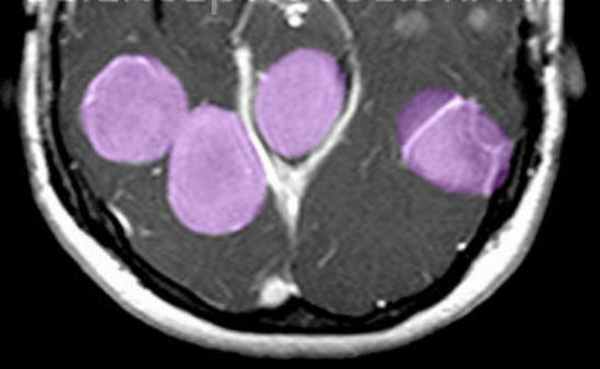

(а) На рисунке аксиального среза изображена распространенная плексиформная нейрофиброма правой половины лица и правой глазницы, вызывающая экзофтальм.

(б) МРТ, Т2-ВИ, режим подавления сигнала от жира, аксиальный срез: в области правого пещеристого синуса определяется крупное многодольчатое объемное образование с распространением через заметно расширенную верхнюю глазничную щель. Обратите внимание на вовлечение кожи волосистой части головы справа. Плексиформные нейрофибромы (ПНФ), локализующиеся внутри и вокруг глазниц, кожи волосистой части головы, редко имеют такую степень вовлечения внутричерепных структур. (а) МРТ, постконтрастное Т1 SPGR-изображение, косая саггитальная реконструкция: у четырехлетнего мальчика с прогрессирующей левосторонней лицевой мышечной слабостью определяется аномальное накопление контрастна вдоль барабанного и нисходящего сосцевидного сегментов левого лицевого нерва.

о Плексиформная нейрофиброма (ПНФ): плохо отграниченное от окружающих структур червеобразное мягкотканное объемное образование с инфильтративным характером роста у пациента с НФ1

о Плексиформная нейрофиброма (ПНФ): глазница (ЧН VI), кожа волосистой части головы, околоушная слюнная железа

о Инфильтративный характер роста, изоинтенсивный на Т1-ВИ сигнал

о Гиперинтенсивный на Т2-ВИ сигнал

о Высокоинтенсивное, несколько гетерогенное контрастирование